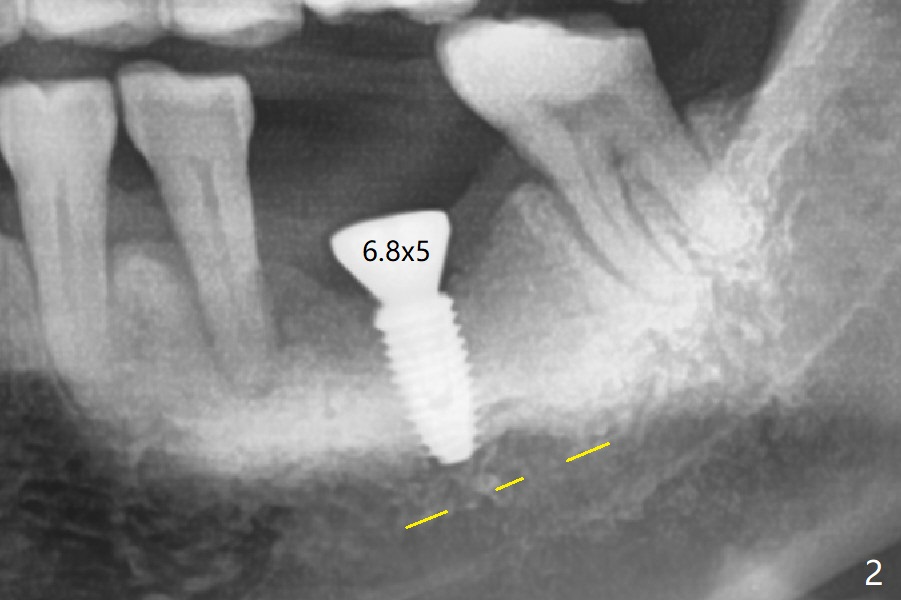

Osteotomy shows two layers of bone. The first one feels slightly less dense than the normal bone (Fig.1 above the red dashed line), while the second one is extremely hard (3-4 mm in depth). For the last 1.5 mm of the osteotomy, the 4.5 mm drill has to be withdrawn for bone shaving removal before finishing the osteotomy. In all the graft bone contributes to implant stability (insertion torque > 50 Ncm). At least the implant is surrounded by the bone with less likelihood of developing periimplantitis. As usual, there is clearance from the Inferior Alveolar Canal (Fig.2 yellow dashed line). After quick surgery, the patient wonders why he does not get a provisional. The advantage of the latter may reduce the chance of shifting of the neighboring teeth (with increased pdl, Fig.2). In fact he requests final restoration in a month. Some of my patients travel a lot. Miao afraid of dentistry. But after #30 implant placement with guide, she is fearless. A permanent crown was delivered in 2 months. Two or 3 months later she returned for #14 guide. Mr. Zheng has the similar situation. He will stay in his home country for 2 months. I want to satisfy him although I have not promised to. Do you have any suggestions?